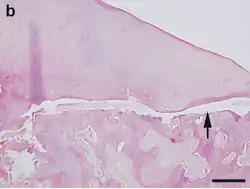

Hematoxylin and eosin staining. Bar = 200 μm.

OCD also is found in animals, and is of particular concern in horses, as there may be a hereditary component in some horse breeds.[97] Feeding for forced growth and selective breeding for increased size are also factors. OCD has also been studied in other animals—mainly dogs, especially the German Shepherd[98]—where it is a common primary cause of elbow dysplasia in medium-large breeds.[99]

In animals, OCD is considered a developmental and metabolic disorder related to cartilage growth and endochondral ossification. Osteochondritis itself signifies the disturbance of the usual growth process of cartilage, and OCD is the term used when this affects joint cartilage causing a fragment to become loose.[100]